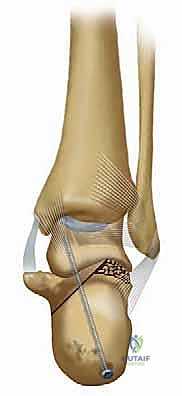

تُظهر الصورة أعلاه فحصاً بالأشعة المقطعية يوضح مدى تعقيد الكسر الأولي والإزاحة التي تحدث، مما يسلط الضوء على التشريح الفوري بعد الإصابة والذي يمهد لسوء الالتئام إذا لم يُعالج بدقة.

3. التصوير المقطعي المحوسب (CT Scan) مع إعادة البناء ثلاثي الأبعاد (3D Reconstruction)

لا يمكن التخطيط لجراحة تصحيح سوء التئام عظم العقب بدون أشعة مقطعية. توفر الأشعة المقطعية رؤية دقيقة للتشريح العظمي المشوه، وتحدد بدقة مكان الانحشار الشظوي، حالة الأسطح المفصلية، ومسار الأوتار. التخطيط ثلاثي الأبعاد يسمح للجراح ببناء نموذج افتراضي للقدم وتحديد أماكن القطع العظمي المطلوبة بدقة مليمترية قبل الدخول إلى غرفة العمليات.